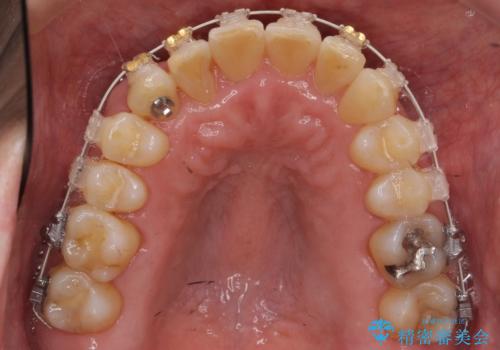

右上の八重歯は、右上の奥歯を矯正用ミニスクリューを用いて遠心移動を行い解消しました。